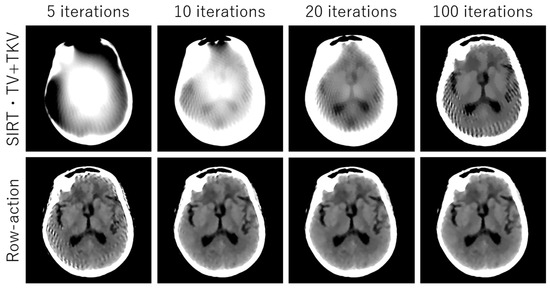

3. Experimental Results

4. Discussion